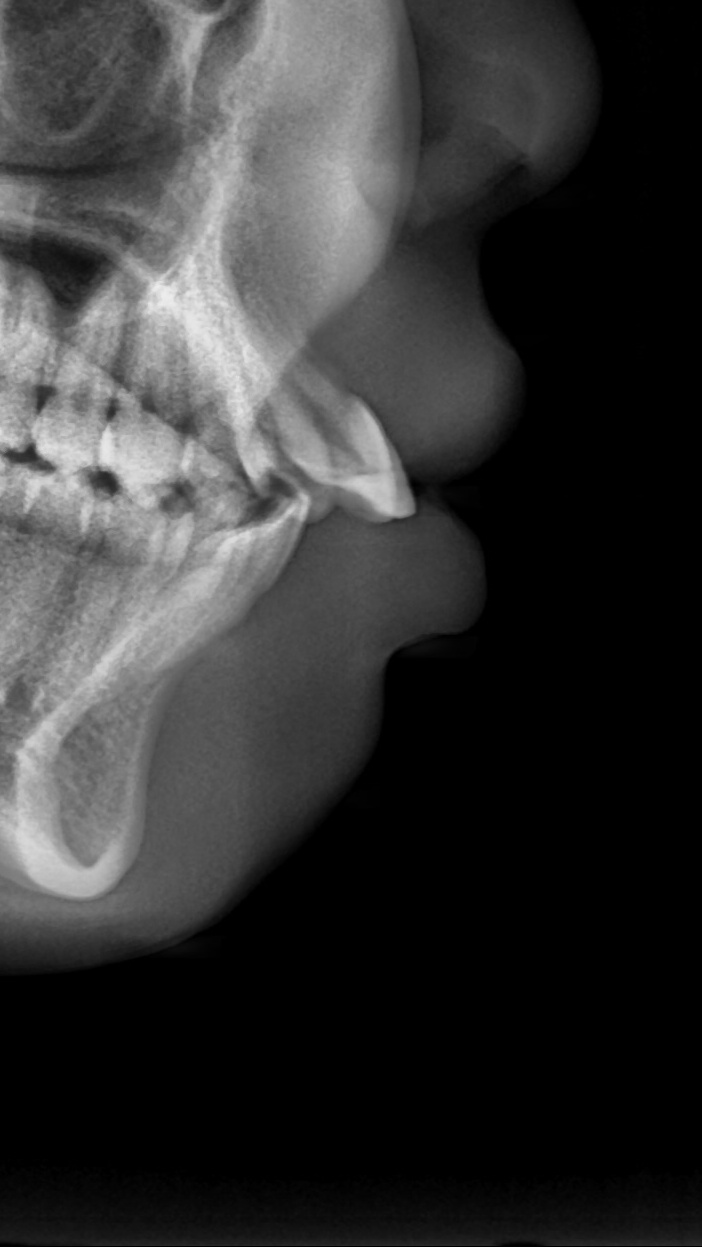

아래쪽 두 번째 어금니(제2대구치)가 선천적으로 없는 결손치로서, 사랑니(제3대구치)가 있으나 앞으로 쓰러져서 잘 안 씹히고 썩어 있습니다.

이런 경우 사랑니를 발치하고 임플란트를 하는 방법도 있으나, 본인 치아를 살리고 싶어하셔서 교정으로 접근하였습니다.

(본원은 교정과 임플란트 모두 다루므로 각 방법의 장단점을 충분히 비교 설명드렸습니다)

부분교정을 통해 누워있던 사랑니를 세웠으나, 씹는 면에 충치가 있습니다.

교정종료 후 보철치료(인레이)를 통해 씹는 기능을 회복시켰습니다.

누워있던 이가 세워져서 음식물이 더 잘 씹히게 되었습니다.

또한 음식물이 끼지 않게 되어 구강위생관리도 원활하게 되었습니다.